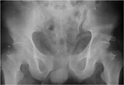

Pelvis kemikleri, insan iskeletinin alt kısmında yer alarak vücut ağırlığını taşır ve iç organları korur. Bu yapı, os coxae, sakrum ve koksiks olmak üzere üç ana bölümden oluşur. Pelvisin anatomisi, hareket kabiliyeti ve denge açısından kritik öneme sahiptir.

Pelvis, insan iskeletinin alt kısmında yer alan ve vücut ağırlığını taşıyan önemli bir yapıdır. Pelvis kemikleri anatomisi, insan vücudunun hareket kabiliyeti, denge ve iç organların korunması açısından kritik bir rol oynamaktadır. Bu makalede pelvis kemiklerinin anatomisi, bileşenleri ve işlevleri detaylı bir şekilde ele alınacaktır. Pelvis'in Yapısı ve FonksiyonuPelvis, genel olarak üç ana bölümden oluşmaktadır: